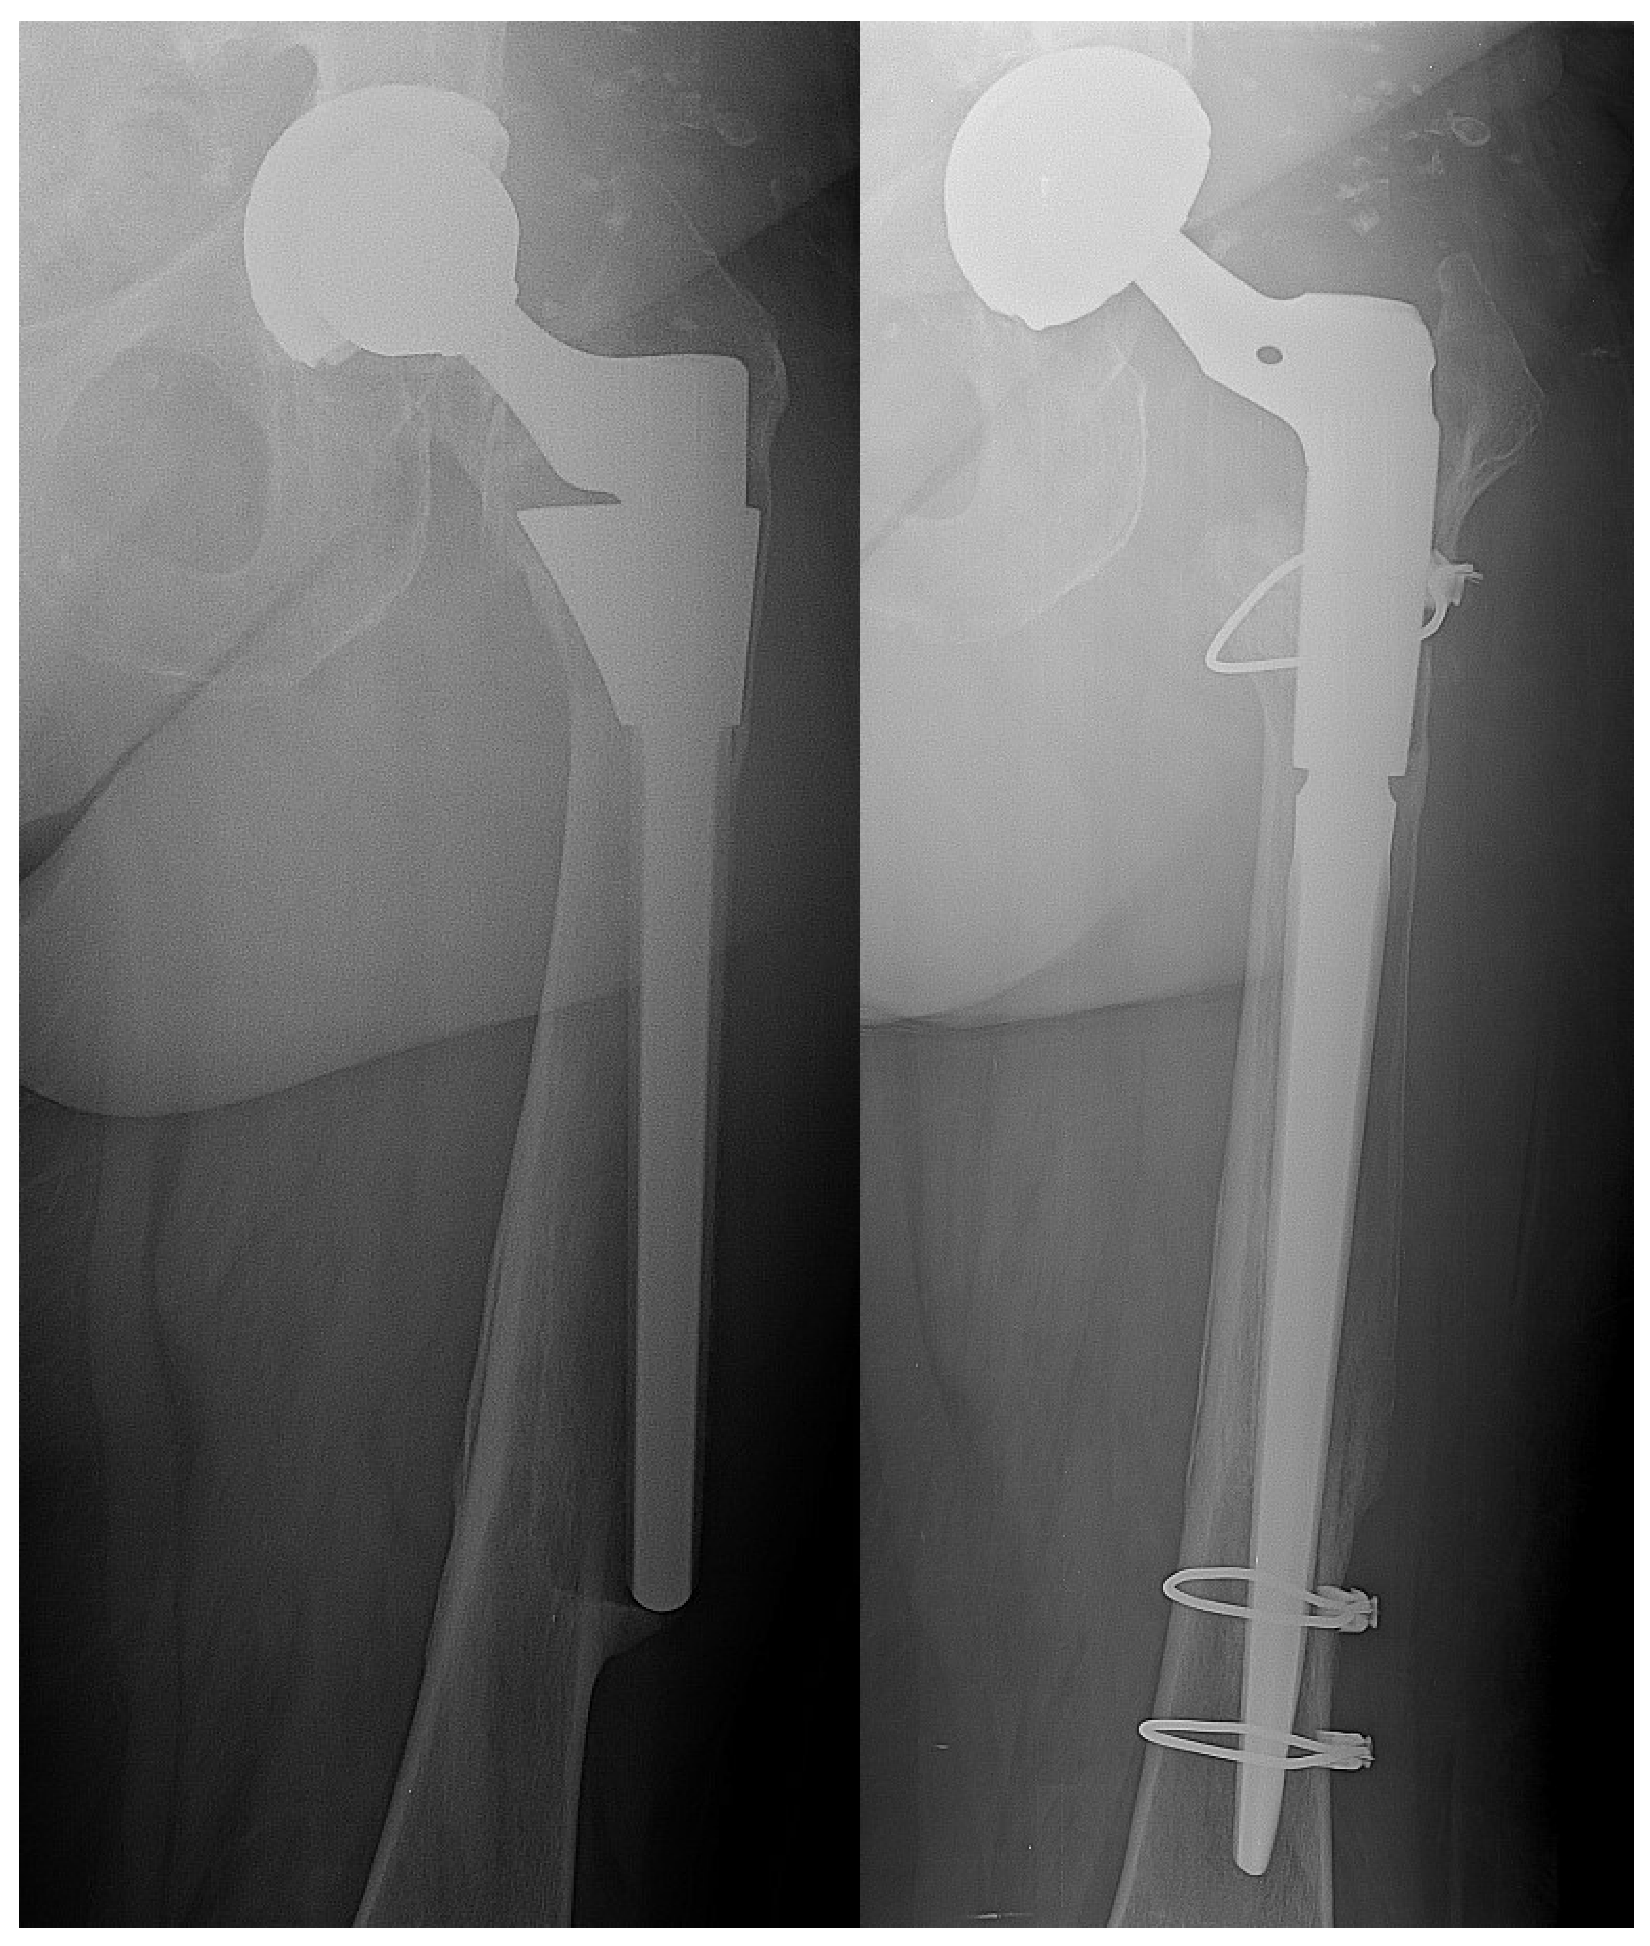

| Periprosthetic Fracture | 5 | 7 | 0.7207 |

| Aseptic Loosening | 4 | 4 | 1 |

| Dislocation | 3 | 1 | 0.6012 |

| Wear | 1 | 2 | 1 |

| ARMD 1 | 0 | 1 | 1 |

| Fixation Failure | 4 | 2 | 0.6562 |

| Stem or shell revision | 5 | 9 | 0.2960 |

| Stem and shell revision | 1 | 0 | 1 |

| Mobile components revision | 1 | 2 | 1 |

| Osteosynthesis (only) | 5 | 4 | 1 |

| Conversion THA | 4 | 2 | 0.6562 |

| + Bone grafting | 3 | 1 | 0.6012 |